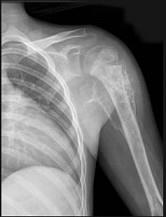

问题 男,28岁,右上臂肿胀、疼痛;无发热,无外伤史,请结合影像图像,选择最可能诊断()

选项 A.骨肉瘤 B.成骨性骨转移瘤 C.化脓性骨髓炎 D.滑膜肉瘤 E.骨巨细胞瘤

答案 A